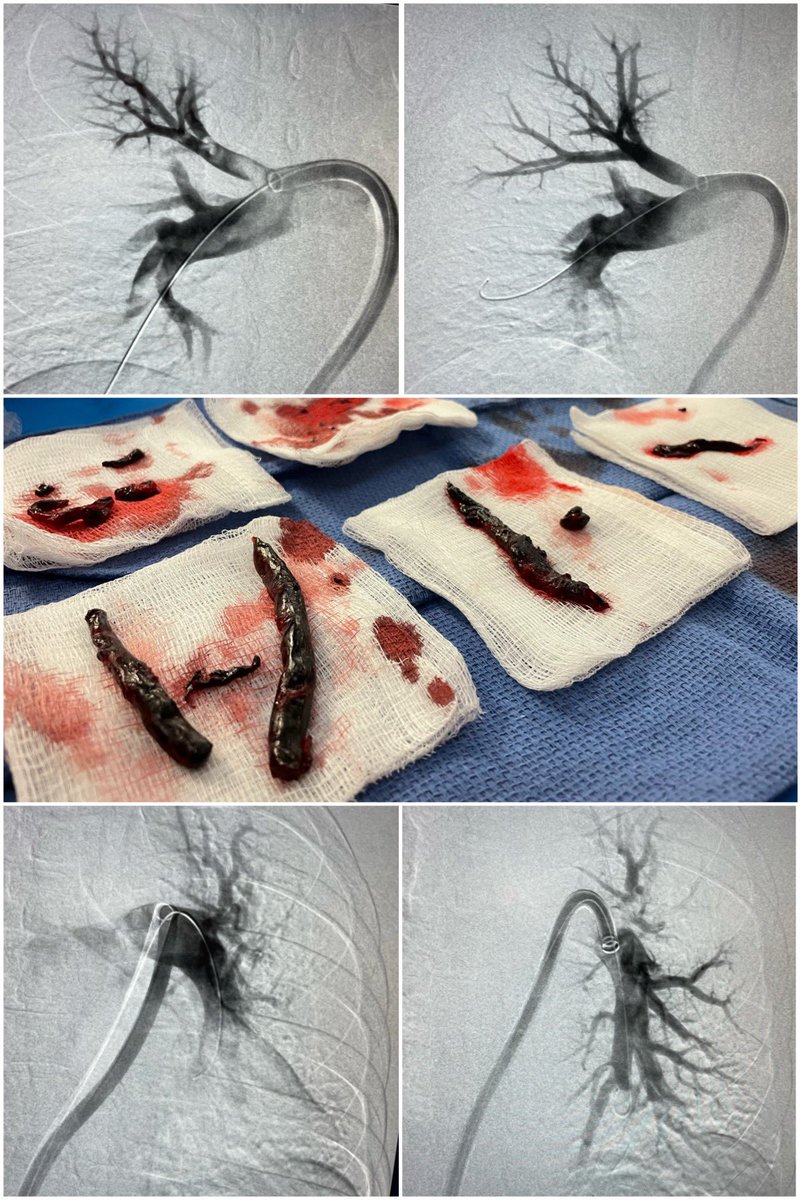

Wear your mask and get vaccinated! COVID associated acute limb ischemia. No distal signals on Doppler. This patient almost lost her leg. SIR RFS SIR ECS Society for Vascular Surgery #irad #vascular #cardiotwitter #COVID #medtwitter